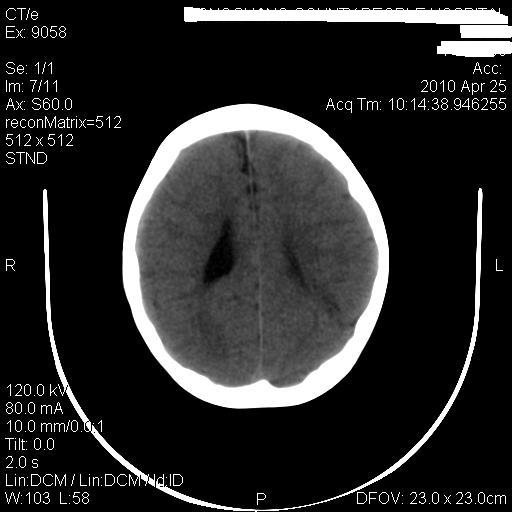

标题: PED3218:3岁女孩,曾有外伤史。未提供前片 [打印本页]

标题: PED3218:3岁女孩,曾有外伤史。未提供前片

发育略有障碍。欢迎大家发言。谢谢!

考虑右侧额顶叶脑软化灶并脑穿通畸形。

考虑:1)右侧额顶叶脑软化灶并脑穿通畸形。2)胼胝体发育不良。

支持考虑:1)右侧额顶叶脑软化灶并脑穿通畸形。2)胼胝体发育不良。

1)右侧额顶叶脑软化灶。2)胼胝体发育不良?

考虑右侧额顶叶软化灶并脑穿通畸形,胼胝体发育不全。

还有脑室周围白质软化症